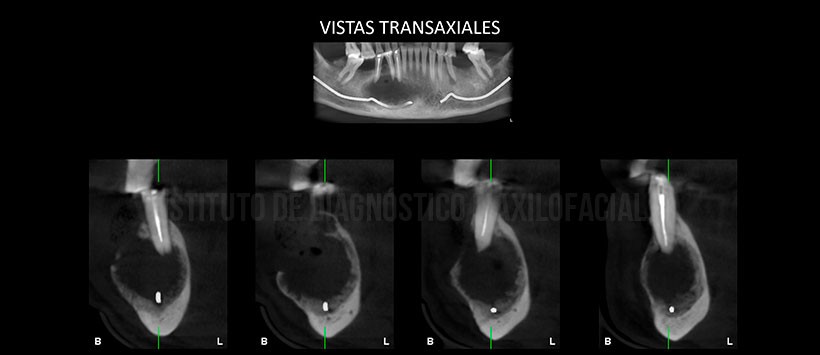

A la evaluación de la tomografía volumétrica de haz cónico (Figura 2, Figura 3 y Figura 4) se evidencia que dicha lesión se extiende desde la pieza 41 hasta mesial de la pieza 47, una disminución de la densidad ósea en su configuración interna, así mismo se observa un leve desplazamiento hacia el reborde basal del conducto dentario inferior, expansión de ambas tablas óseas (a predomino de la tabla ósea vestibular). Así mismo se visualiza una imagen hipodensa de forma redondeada dentro de la lesión (enfisema) a consecuencia de la manipulación en zona de la tabla ósea vestibular (perdida de continuidad).